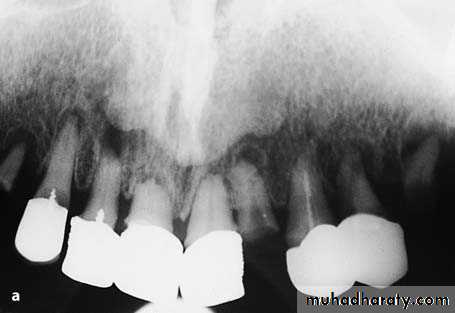

preprosthatic surgery

a Radiograph of maxillary teeth, after whose removal smoothing of alveolar bone is required. b Clinical photograph of teeth to be extracted